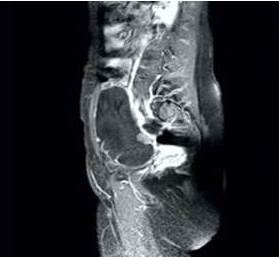

La ecografía detectó tumor ovárico derecho de 9 cm de diámetro, de tipo mixto localizada anterior al útero con porción quística anecoica con paredes finas, regulares, tabiques gruesos y área solida en la parte inferior. La ecografía Doppler demostró vascularización escasa y periférica. Las imágenes de resonancia magnética confirmaron las características de la lesión de 11 cm x 8 cm, con tabiques gruesos y nódulos periféricos, supravesical y anterolateral al útero y que parecía originarse del ovario derecho. El útero y anexo izquierdo estaban normales, sin evidencia de linfadenopatías pélvicas (Figura 1). Los valores de marcadores tumorales fueron antígeno carcinoembriogénico 8,1 ng/mL, CA19-9 1170 y Ca-125 485 UI/mL. En vista de la posibilidad de una neoplasia maligna de posible origen ovárico se decide realizar la cirugía.